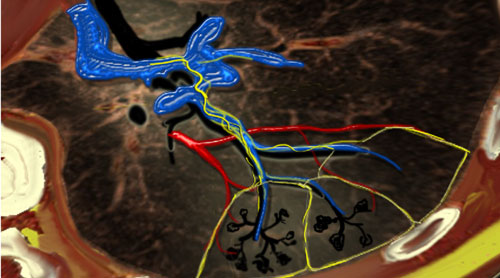

Liver - Segmental Anatomy